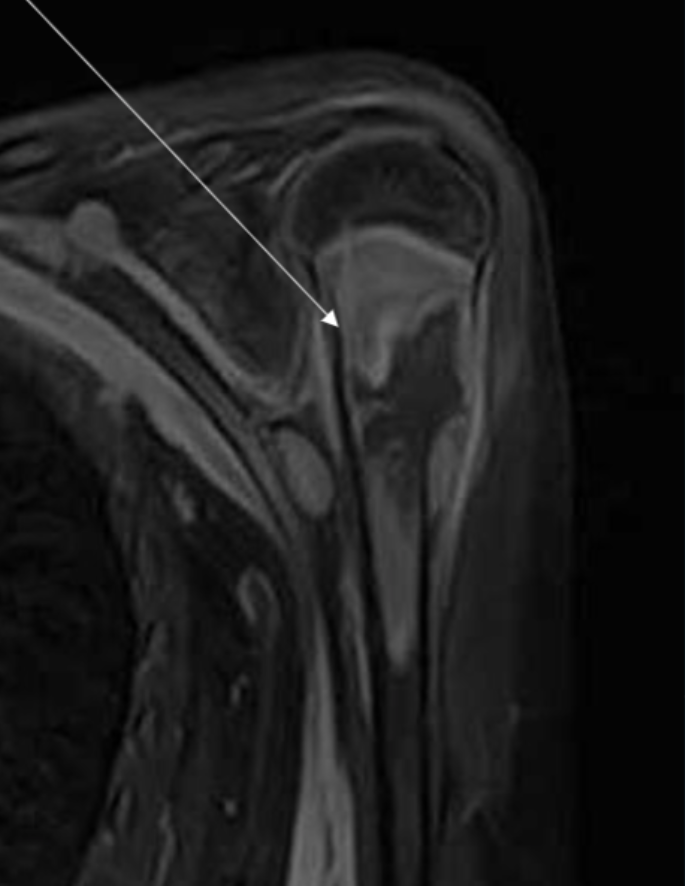

Describe the pathology indicated by the arrow (Ax T1).

Bankart lesion